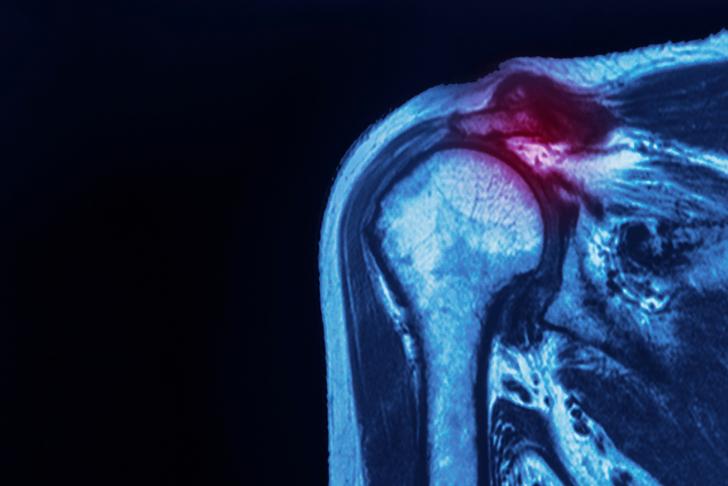

Rotator Cuff Injuries

Rotator cuff injuries are a common cause of shoulder pain and can result from tears, strains, or inflammation of the tendons and muscles that make up the rotator cuff [[2]]. These injuries often occur due to repetitive overhead movements or trauma and can cause pain, weakness, and limited range of motion in the shoulder.